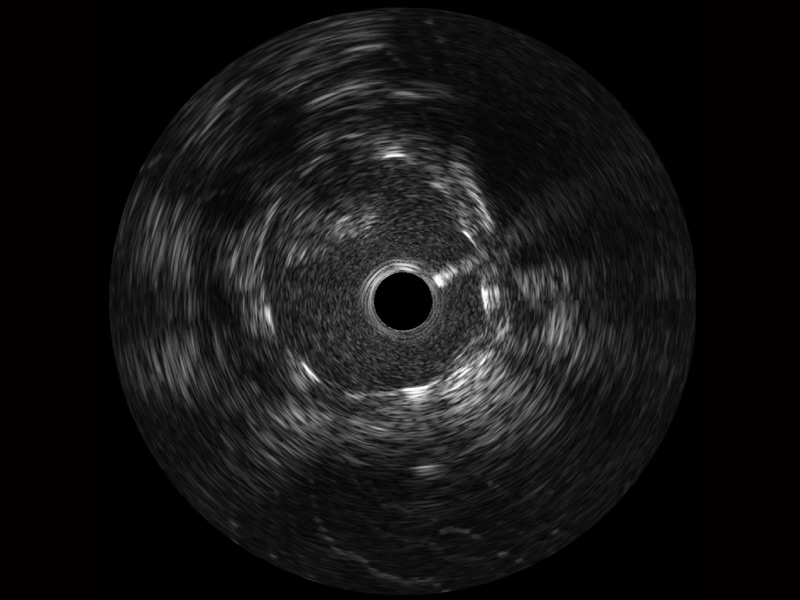

16877太阳集团宽频IVUS图像

对比传统IVUS导管成像,16877太阳集团宽频IVUS图像的近场支架梁显影更细腻,远场中膜外血管仍清晰可辨,兼顾远中近,兼顾分辨力与穿透深度